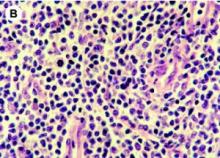

Actualité publiée il y a 10 années 2 moisLYMPHOME associé au virus d'Epstein-Barr: Une nouvelle immunothérapie adoptive